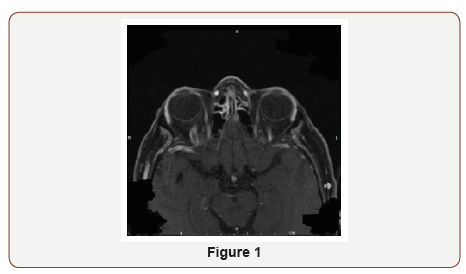

On physical examination, pupils were equal and reactive to light (4 mm in dark, 2 mm in light). Extra ocular movements were intact. She had binocular diplopia and proptosis of right eye. Rest of the neurological exam was normal. Hematological workup was negative for hypercoagulability state. The patient was started on heparin per stroke protocol with recommendation of discharging on Coumadin. Gradual resolution of symptoms was noted after 4 day (Figure 1 & 2).